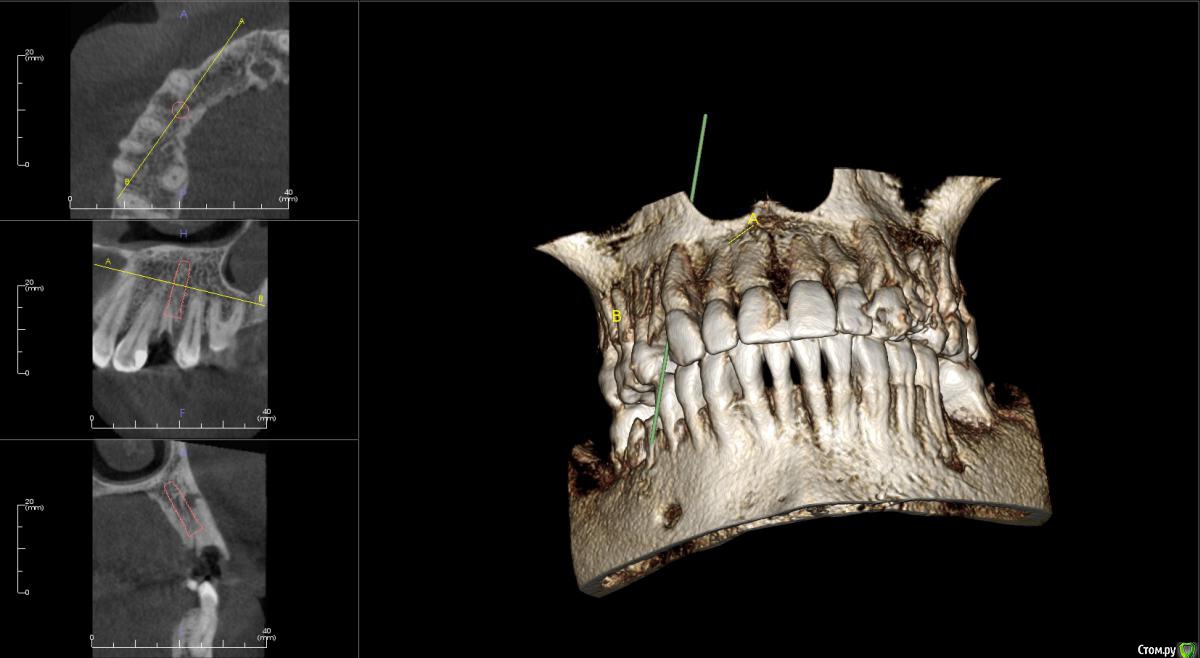

faity Опубликовано 10 ноября, 2015 Поделиться Опубликовано 10 ноября, 2015 По сути переапикальные изменения обусловленны инфекцией непосредственно в каналах и после удаления причинного зуба, даже при наличии остаточной МО в костной ткани это никак не мешает приживлению импланта.Но к сожалению мои выводы основанны исключительно на литературных данных в этой области, т.к. я не дядя Карен и не имею возможности проводит гистологические исследования По топику: апекс импланта я бы немного вестибулярнее расположил, чтобы шахта выходила на бугры, а не на вестибулярную стенку и по длине такой, чтобы якорнулся в кости хотя бы на 1 мм Ссылка на комментарий

kamranchick Опубликовано 10 ноября, 2015 Автор Поделиться Опубликовано 10 ноября, 2015 По сути переапикальные изменения обусловленны инфекцией непосредственно в каналах и после удаления причинного зуба, даже при наличии остаточной МО в костной ткани это никак не мешает приживлению импланта.Но к сожалению мои выводы основанны исключительно на литературных данных в этой области, т.к. я не дядя Карен и не имею возможности проводит гистологические исследования По топику: апекс импланта я бы немного вестибулярнее расположил, чтобы шахта выходила на бугры, а не на вестибулярную стенку и по длине такой, чтобы якорнулся в кости хотя бы на 1 ммПридется выбирать. либо идти по небной стенке, либо в правильной ортопедической позиции, а можно ли сразу 2 зайца убить в данном случае? боюсь при удалении дефект будет большим. Ссылка на комментарий

faity Опубликовано 10 ноября, 2015 Поделиться Опубликовано 10 ноября, 2015 засверлитесь в правильной позиции, запакуйте графт, дойдите финишным сверлом до апекса и поставьте винт.и винт и объем и торк. сст туда посадите вообще отлично будет. Ссылка на комментарий

St_Klaus Опубликовано 10 ноября, 2015 Поделиться Опубликовано 10 ноября, 2015 По топику: апекс импланта я бы немного вестибулярнее расположил, чтобы шахта выходила на бугры, а не на вестибулярную стенку и по длине такой, чтобы якорнулся в кости хотя бы на 1 мм +1. Ссылка на комментарий